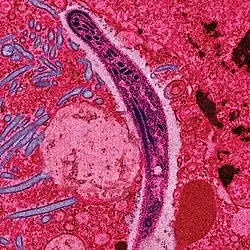

Immunization

The term immunization refers to rendering an organism immune to a specific communicable disease. Immunizations work by triggering the human body to produce antibodies that will help fight a particular disease. The antibody response is created by injecting a small amount of either a dead or live virus, (depending on the virus) into the person receiving the immunization in order to initialize a immune system response to the virus. Therefore in the future if the person who was immunized was exposed to the virus, he or she would already have the antibodies to fend off the virus. Along with the introduction and transmission of many new complex diseases, population growth and the globalization of medicine has brought about the eradication of many previously devastating disorders, including smallpox and polio, through wider availability of immunizations. Many parents in Western countries routinely schedule immunizations for their children to prevent them from contracting a specific communicable disease. While many vaccinations are routine and readily available only in developed nations, the continued globalization of medicine will eventually have a dramatic effect on the improvement of health care in developing countries.[8] [9]

There is a great deal of controversy over vaccination in some cultures regarding the morality, ethics, necessity, safety, and practicality of vaccination have led some parents to keep their children from being vaccinated. Opponents of vaccines claim that they are dangerous, ineffective, and infringe on personal rights.

And example of this is the current debate over whether or not certain vaccines cause autism in children. There is a small but dedicated group of doctors who claim that vaccines may be linked to the onset of autism in children. As a result many parents are insisting their children be exempt from the mandatory vaccines although there are no medical findings which prove the link between the two.[10]